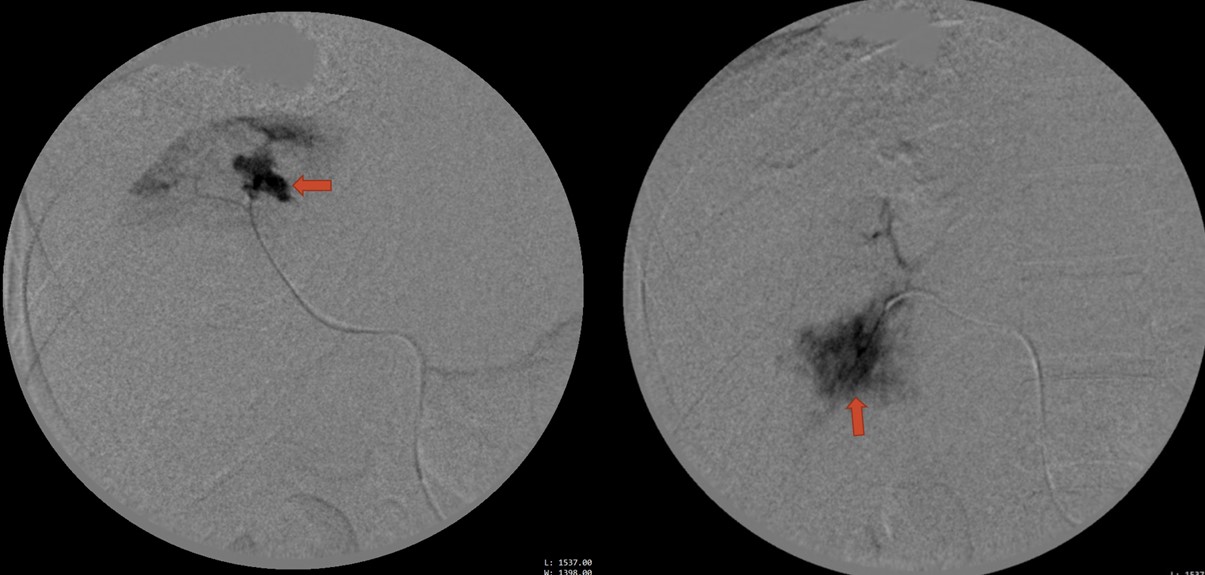

Hình 4. Hình ảnh chụp động mạch gan sau can thiệp cho thấy không còn các ổ xuất huyết nhu mô gan.